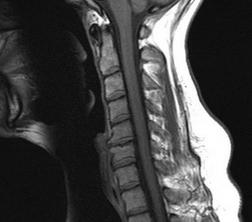

近日,全球最大的骨科及醫療科技公司Stryker研發的3D打印鈦金屬後路腰椎間盤得到了FDA的許可,為(wei) 該公司的發展奠定了堅實的基礎。